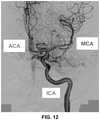

FIG. 12 illustrates an example image of a vasculature and relevant anatomical information that can be used by an embodiment(s) of a system and/or method for robotic endovascular intervention.

In some embodiments, the catheter is then directed by the system along a number of directories depending on the location of the targeted clot. For example, in some embodiments, the number of directories is six (e.g., 3 on the right, 3 on the left). For example, in arrangements where the clot or other targeted location is in left middle cerebral artery (MCA), the pathway can be: aortic arch to left common carotid to left internal carotid artery to the point of bifurcation to MCA.

According to other embodiments, where the clot or other targeted location is in the left anterior cerebral artery (ACA), the pathway can be: aortic arch to left common carotid artery to left internal carotid to the point of bifurcation to ACA.